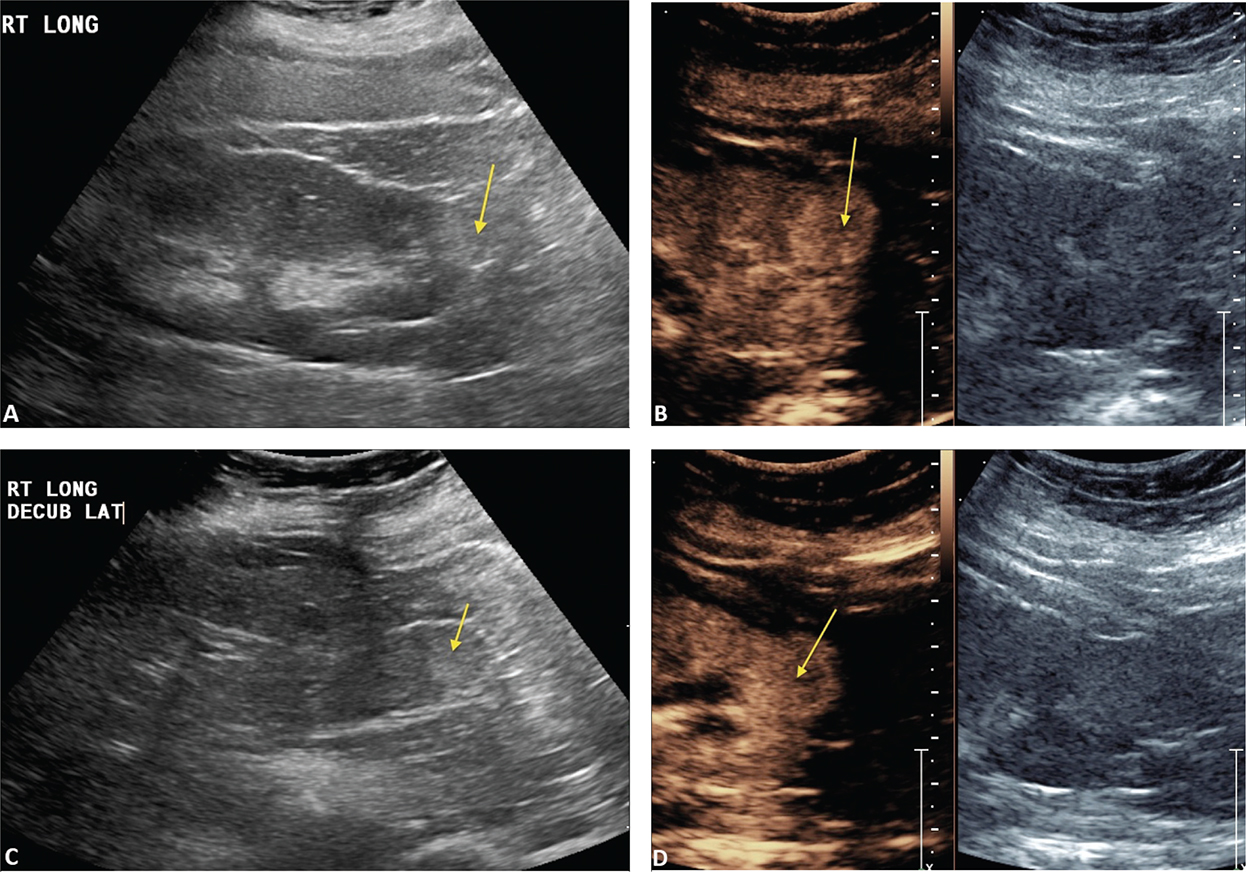

Occasionally a complete ablation cannot be obtained. This is often from significant blood flow to the mass or the mass adjacent to the collection system which acts as heat sinks and does not allow for adequate temperature to ablate the tumor. Figure 5 demonstrates a renal mass on the B-mode image (A) and the CEUS image (B). Immediately post-RFA, the B-mode (C) and CEUS (D) demonstrate minimal ablation of the tumor.

Figure 5. Failed ablation. Patient has history of prior left nephrectomy for RCC and presented with right renal mass. (A) Gray scale image of mass (arrow) pre-ablation. (B) CEUS demonstrating increased flow in tumor (arrow) at inferior pole of right kidney. (C) Gray scale image post-RFA of the mass (arrow). (D) CEUS post-RFA demonstrating flow throughout the tumor (arrow), indicating failed RFA.